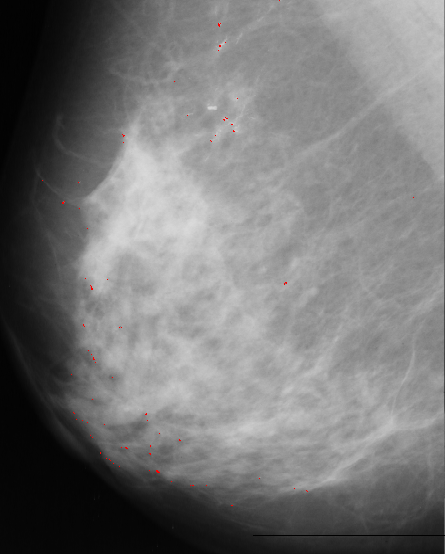

Median filter approach is based on assumption that microcalcification are small spots with higher intensity then surrounding background. First we apply median filter to bright area of the original image. Median filter eliminates small isolated spots including microcalcifications. Next step is to bring them back by substracting filtered image from original one. Since we are only interested in spots brighter than background we keep only positive resulting values and set other to zero. Our next step is to match resulting image with 5x5 template. It has bell shape with value of 1 at the central point, which we expect to have a best fit at the position of microcalcification.

Template, multiplied with pixel value at current position, is substracted from median filtered image. The results are normalized, thresholded and added to original image to point to possible position of microcalcification.

A result of this approach is:

Figure 4.